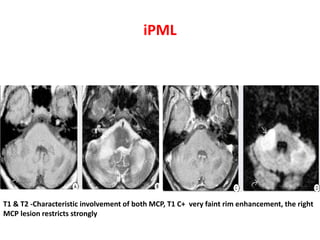

T1 & T2 -Characteristic involvement of both MCP, T1 C+ very faint rim enhancement, the right

MCP lesion restricts strongly

iPML T1 & T2-Characteristic involvement of both MCP, T1 C+ very faint rim enhancement, the right MCP lesion restricts strongly